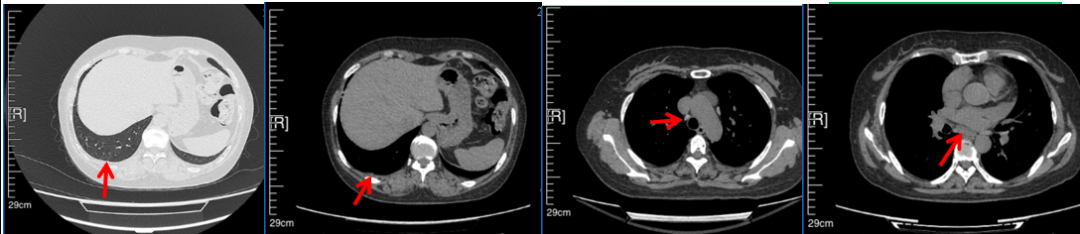

56岁,女性,无吸烟史饮酒史,既往体健。2023年02月患者体检发现肺占位性病变,胸部增强CT:右肺下叶后基底段结节;右侧锁骨上及纵隔内多发淋巴结肿大。PET-CT:右肺下叶周围型肺癌可能性大;1R、2L、3P、4R、4L及7组淋巴结转移可能性大。2023年02月就诊于本院胸外科行超声胃镜下纵隔肿物穿刺活检术,病理:结合免疫组化,符合肺腺癌。行NGS基因检测:EML4:exon20-ALK:exon20融合。PD-L1(克隆号22C3)TPS=55%。

2023年2月20日基线检查

2024年6月复查PR(最佳疗效)